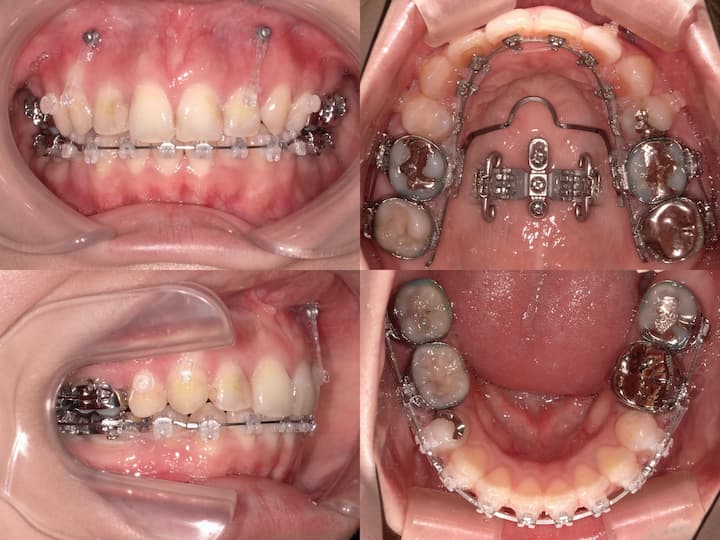

開咬(オープンバイト)のマウスピース矯正治療

Before

After

治療期間: 1年6ヶ月

前歯が噛み合っていないため、上顎臼歯を圧下(上方向に移動)し、上顎前歯は挺出(下方向に移動)して治療を行いました。

大臼歯の圧下と上顎前歯の挺出

上顎大臼歯の圧下(上方向に移動)と上顎前歯の挺出(縦に伸ばす)を行いました。下顎前歯は極力挺出させず、下顎骨の回転により前歯を噛み合わせるような治療計画を立てました。

開咬(オープンバイト)は後戻りにより、治療後に再び前歯が噛み合わなくなるリスクがあります。大臼歯の圧下のみや前歯の挺出のみの治療ではそれぞれの歯の移動量が大きくなり後戻りのリスクが大きくなります。 したがって大臼歯の圧下と前歯の挺出を組み合わせることでそれぞれの歯の動きをできるだけ小さくして後戻りのリスクを減らしています。このケースでは治療終了2年後に前歯が噛み合う状態を維持できています。